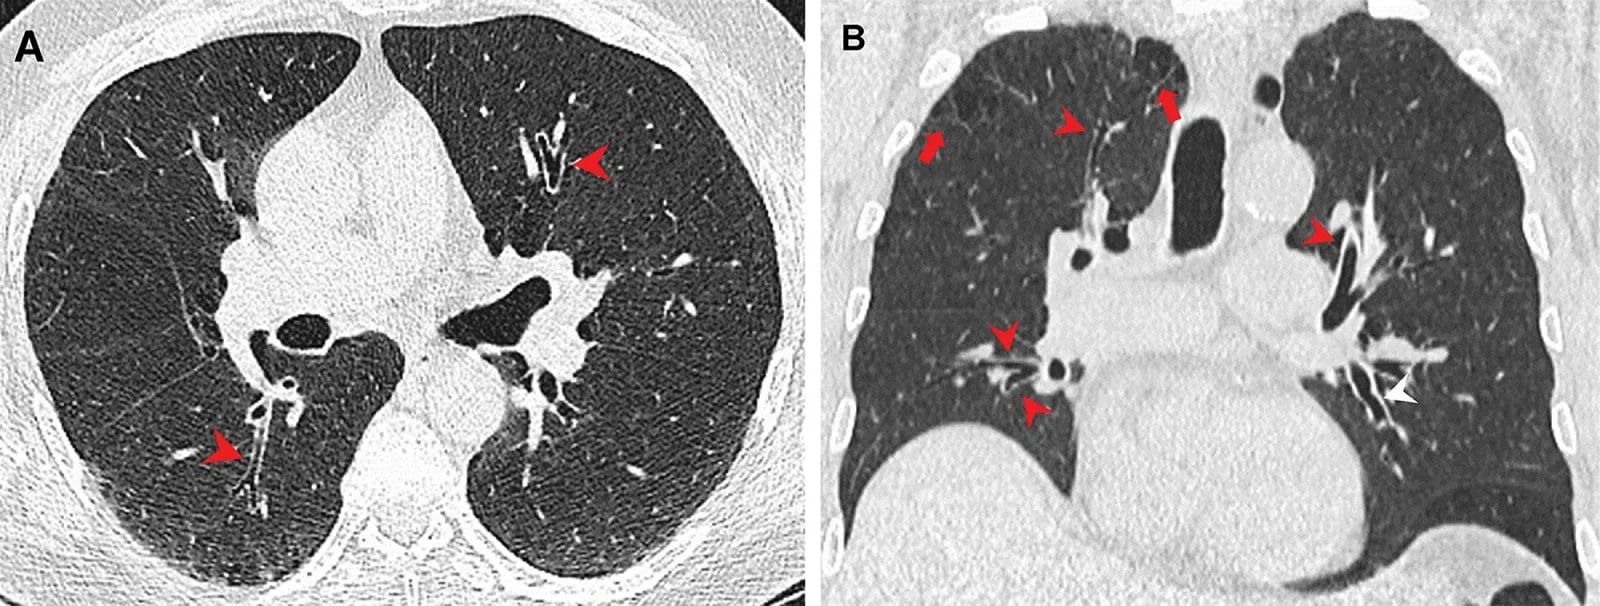

Jej zespół porównał wyniki tomografii komputerowej klatki piersiowej 56 palaczy marihuany z wynikami 57 niepalących osób z grupy kontrolnej i 33 osób zażywających tytoń. Okazało się, że 75 proc. palaczy marihuany miało rozedmę – w porównaniu do 67 proc. wśród palaczy tytoniu. Zapalenie dróg oddechowych również występowało częściej u palaczy marihuany niż tytoniu. To samo dotyczyło ginekomastii, czyli powiększenia piersi u mężczyzn, które wynika z braku równowagi hormonalnej. Wyniki były zaskakujące, zwłaszcza, że pacjenci z grupy wyłącznie tytoniowej mieli bogatą historię palenia.

Szkodliwość marihuany dla płuc może wynikać z faktu, że jest palona bez filtra, co sprawia, że więcej cząstek stałych dociera do dróg oddechowych. Ponadto, marihuana jest wdychana z dłuższym wstrzymaniem oddechu niż dym tytoniowy.

Kanadyjscy uczeni wskazują, że jeden joint odkłada w płucach cztery razy więcej cząstek stałych niż jeden papieros. To prawdopodobnie one są substancjami drażniącymi nasze drogi oddechowe.